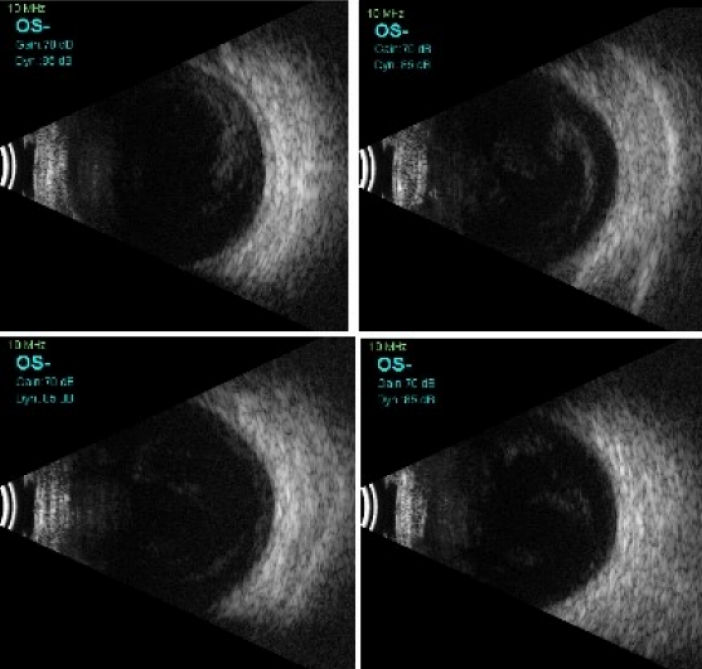

An 11-year-old boy presented to us with complaints of sudden decrease of vision, redness and white discoloration of the cornea in the left eye for the previous three days. The patient gave history of injury with a needle in his left eye. On examination, his best corrected visual acuity (BCVA) was 20/20 in the right eye and hand movement (HM) in the left eye. Intraocular pressure (IOP) with Goldmann applanation tonometry was 18 mm of Hg in both eyes. Right-eye examination was unremarkable. In the left eye, the lids were edematous, the conjunctiva was congested, the cornea had stromal edema and SPKs. 1 mm mobile hypopyon with fibrin was also present in the patient’s left eye. There was no view of fundus. Ultrasound B-scan revealed moderate numbers of moderate reflective dot and clump echoes in all quadrants (Figure 1 [Fig. 1]). The clinical diagnosis of post-traumatic endophthalmitis was made. The patient underwent pars plana vitrectomy and vitreous biopsy, and was given intravitreal antibiotics (vancomycin 1 mg/0.1 ml, ceftazidime 2.25 mg/0.1 ml, voriconazole 0.1 mg/0.1 ml). Vitreous aspirates were inoculated on chocolate agar (CA), blood agar (BA), thioglycolate broth, Sabaroud’s dextrose agar, and brain heart infusion broth (BHIB), and were sent for Gram and KOH stain. Direct mount on Gram stain showed Gram-variable cocci with plenty of polymorphonuclear cells in oil immersion field. On the 3rd day, significant growth was observed on BA and CA, and turbidity was found in BHIB (Figure 2 [Fig. 2]). Colonies on BA and CA were translucent, small, easy to crumble, and had a waxy surface (Figure 3 [Fig. 3]). The isolate was identified as genus Moraxella, and subculture was sent for species identification with the VITEK 2 (version 5.02) system (BioMerieux, USA). However, the species was not determined by the VITEK 2 system. Antibiotic sensitivity was determined by the Kirby-Bauer disc diffusion method on blood agar. The isolate was found to be sensitive for amikacin, ceftriaxone, ceftazidime, chloramphenicol, and tobramycin, and was resistant to vancomycin and linezolid (Figure 4 [Fig. 4]). Medications were changed as per the culture and sensitivity reports. Intravitreal ceftazidime (2.25 mg/0.1 ml) and dexamethasone (0.4 mg/0.1 ml) was given. The patient responded well to the treatment, and his BCVA improved to 20/25 at two weeks follow-up. Thereafter, topical antibiotics were reduced in frequency. At 1 month follow-up, the patient’s visual acuity was 20/20 with no complaints.

Figure 1: Transverse B-scan of all quadrants showing medium reflective dot and clump echoes in all quadrants in vitreous cavity